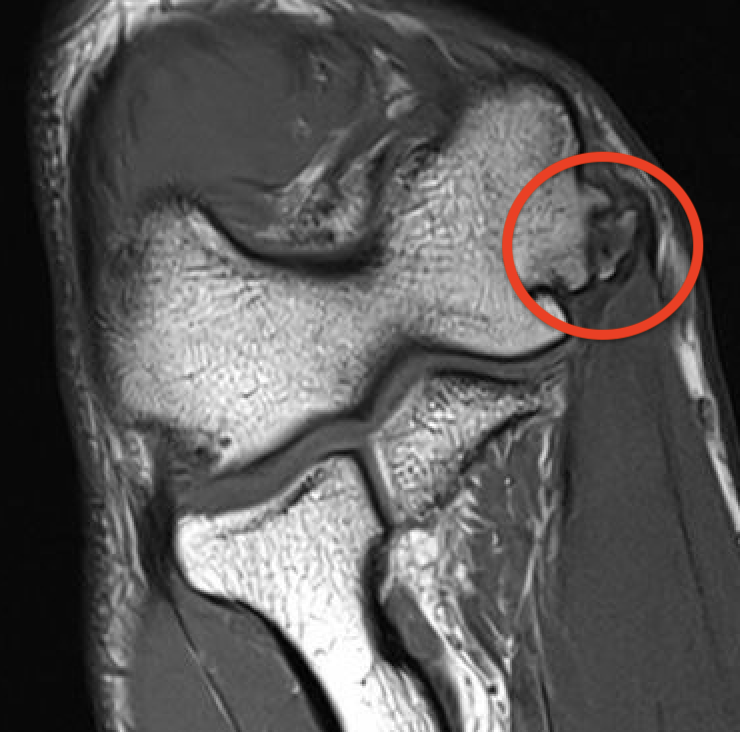

MRI

Intact

Grading of tears

Proximal / midsubstance / distal injury

Partial tears - low grade versus high grade

Complete tears

Acute full thickness UCL tear

High grade partial distal UCL tear

Bony avulsion UCL complex medial epicondyle

Bony avulsion UCL sublime tubercle